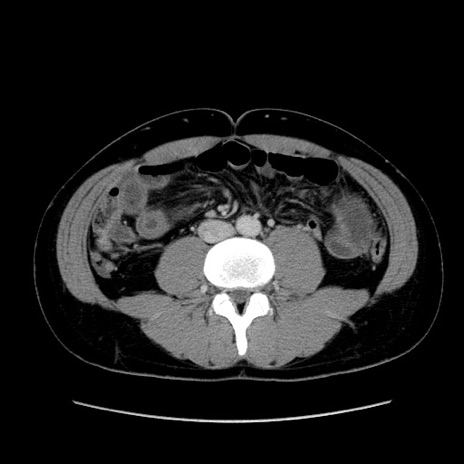

症例36(横断像)

【症例】20歳代 男性

【主訴】心窩部痛

【現病歴】今朝より上腹部痛あり。一旦軽快していたが再度出現したため救急要請。昨日夕に白身の魚を含む刺身を食べた。

【身体所見】BP 136/89mmHg、HR 74/min、BT 37.0℃、腹部:膨満、軟、心窩部に圧痛あり。反跳痛なし、筋性防御なし、腸雑音やや亢進あり。

【データ】WBC 17700、CRP 0.48